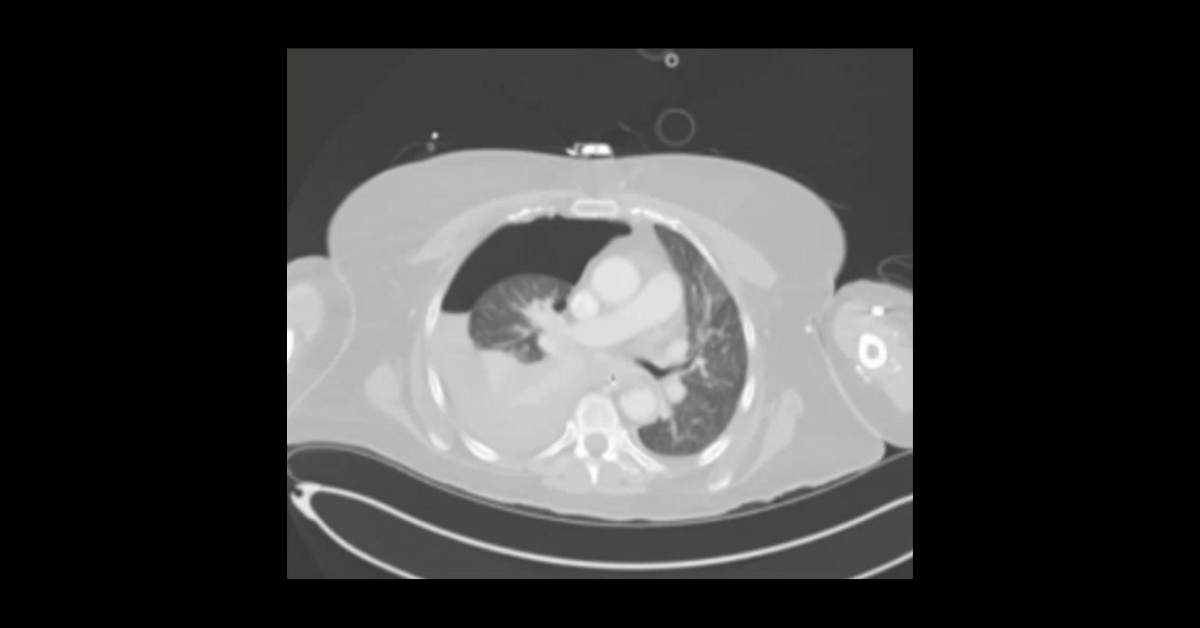

A collection of thoracic CT cases demonstrating a variety of thoracic injuries.

1. Learn the importance of aortic evaluation in trauma imaging.

3. Learn the different anatomic gas collections associated with bronchial injuries.